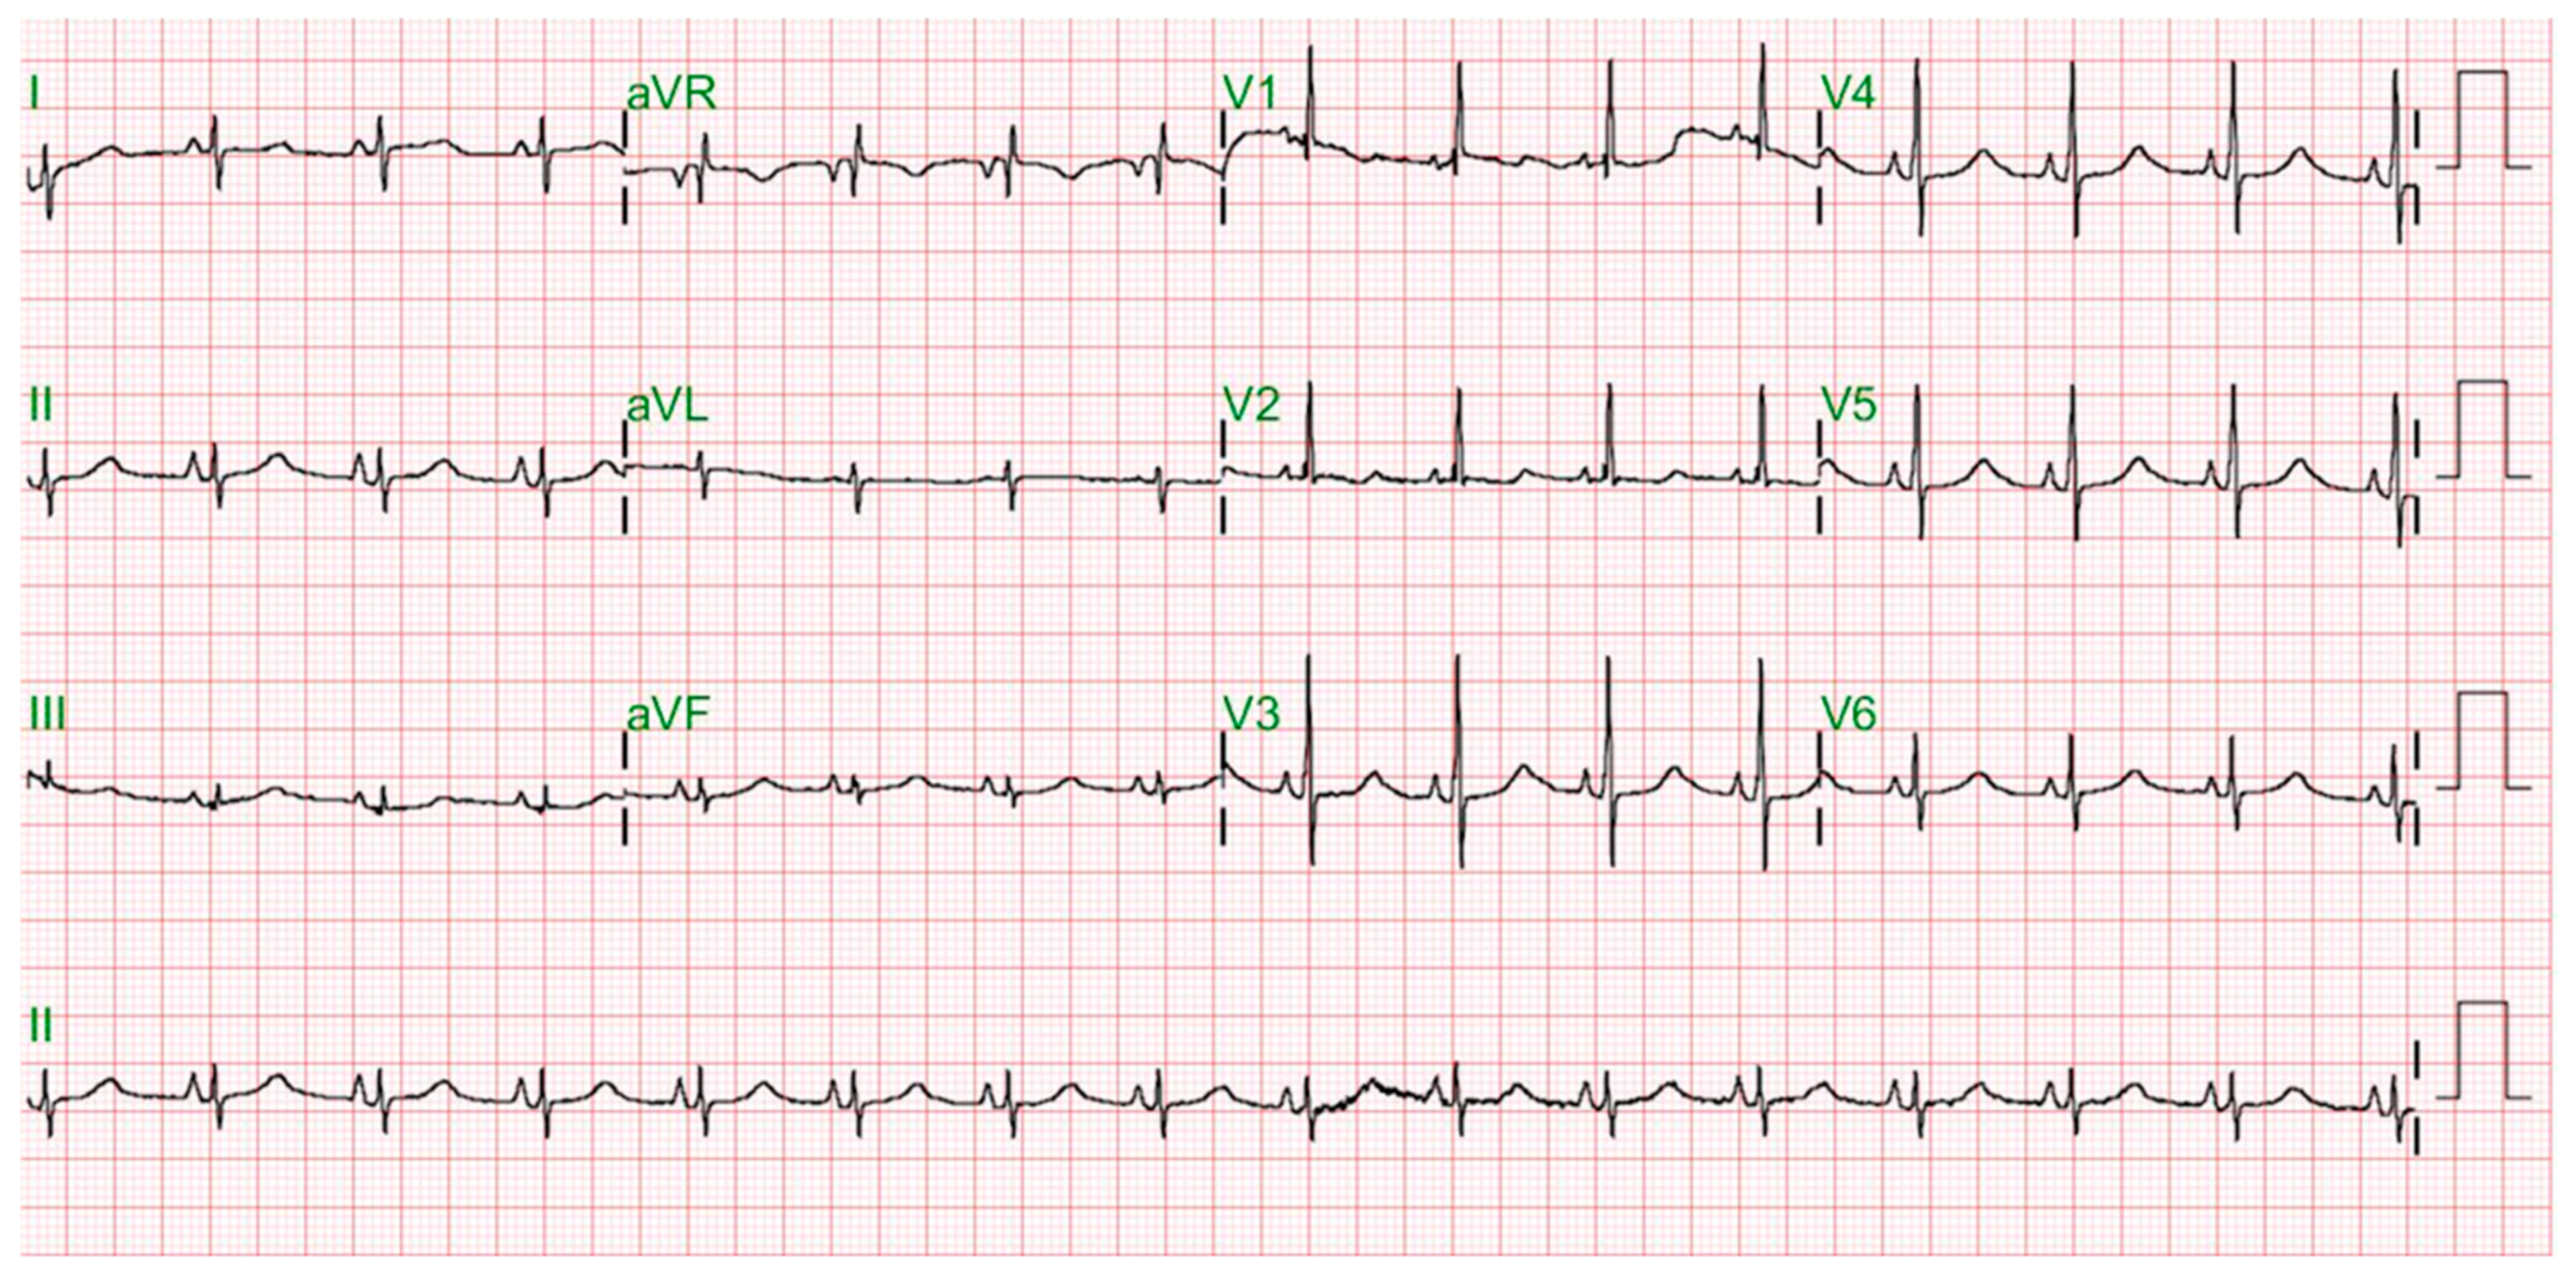

2. Case Report